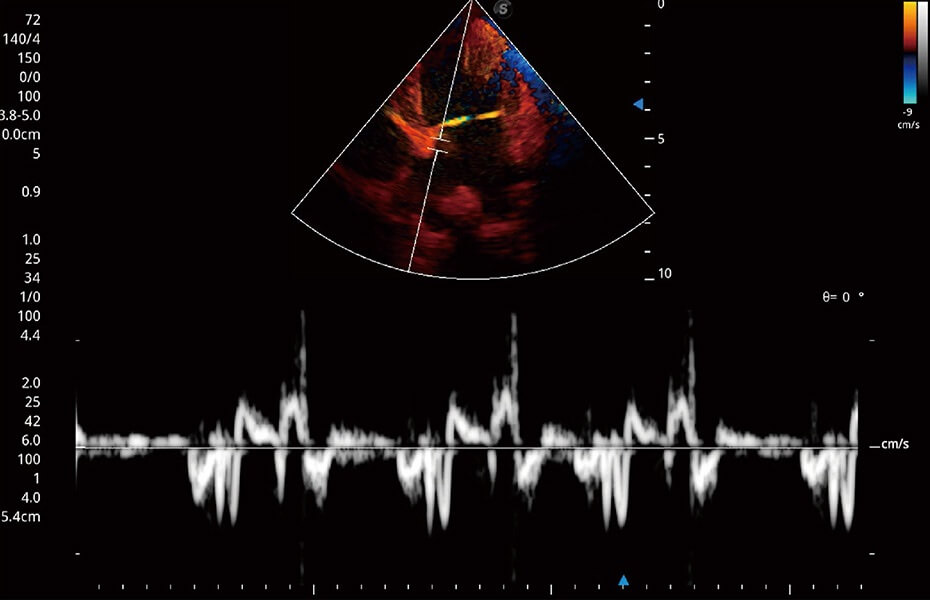

ProPet 60 作為一款高端臺(tái)式動(dòng)物超聲設(shè)備,為動(dòng)物醫(yī)生的日常診斷提供了一系列貼合動(dòng)物臨床需求、解決臨床實(shí)際問(wèn)題的高級(jí)成像功能。憑借全系列高清探頭,滿(mǎn)足醫(yī)生對(duì)腹部、心臟、生殖、淺表、肌骨等成像的所有需求,切實(shí)幫助您提升檢查效率,提高診斷信心。